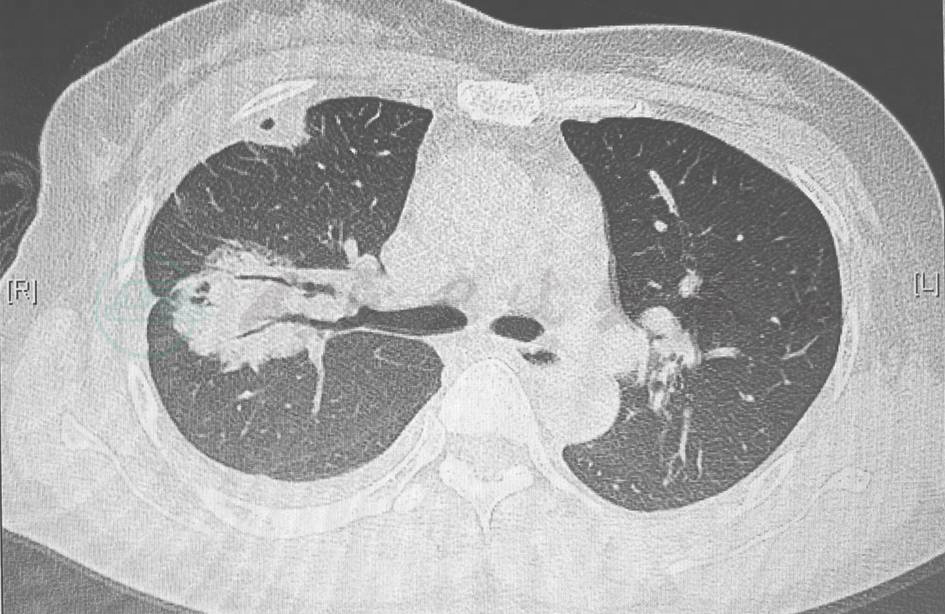

病毒性肺炎:严重急性呼吸道综合征(severe acute respiratory syndrome,SARS)、中东呼吸综合征(middle east respiratory syndrome,MERS)或H1N1等流感病毒(图1)所致的病毒性肺炎,常发病急骤,胸部影像学表现主要为间质性病变,可在数天内进展为“白肺”。腺病毒所致的病毒性肺炎可出现肺实变表现,该病多发生于儿童,但也有成年人发病的报道,除累及肺部以外,还可累及肝、肾、血液系统等,其病程有自限性。本例患者的临床表现与上述情况不符,可检测呼吸道病原协助鉴别。

图1 H1N1感染胸部影像学表现

胸部CT可见双肺多发小斑片磨玻璃实变影